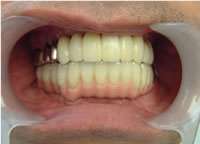

19.下は作った最終本物の歯が入りました。

これで治療終了。

開口器を入れた口元

治療完了

平成21年1月29日

(治療期間:1年7ヶ月)